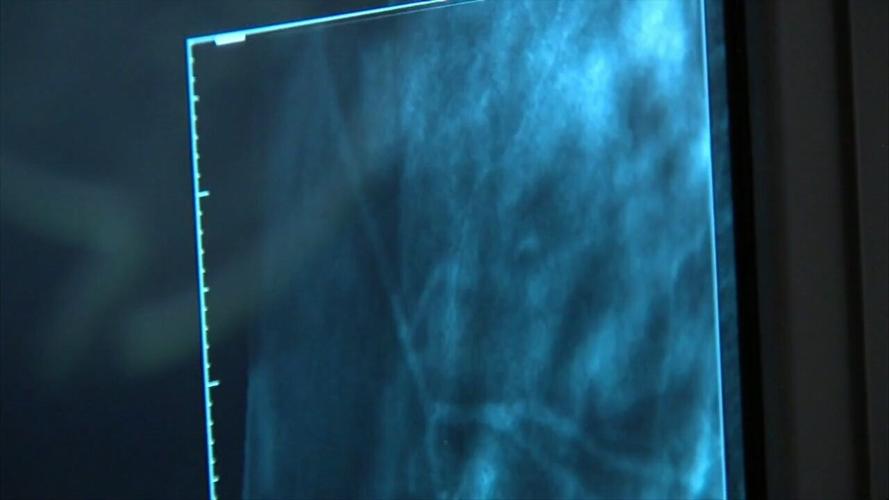

Nearly 1 in 8 women will face a breast cancer diagnosis, however, the death rate among them has decreased due to early cancer screenings. Health officials say that making healthy lifestyle choices can improve survival rates including physical activity. The medical center is holding their first "I Pink I Can" 5K Run/Walk to bring awareness to breast cancer and early detection.